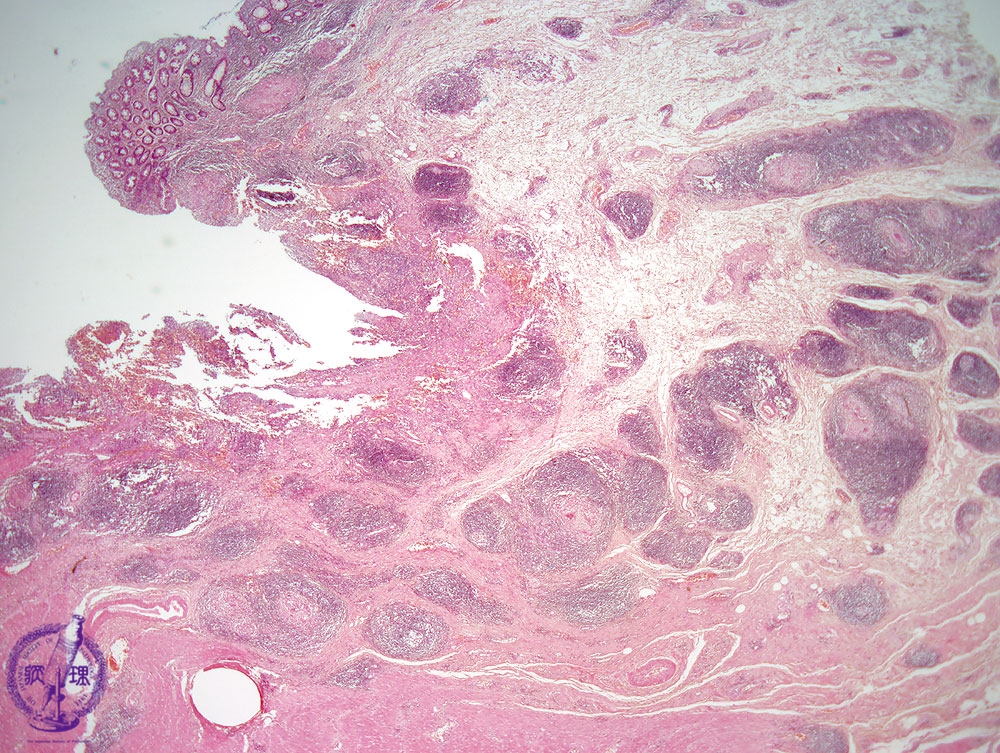

Microscopic view (H&E stain, low power): Multiple caseating granulomas are seen forming in the bed of an ulcer which shows characteristic undermined edges.

Click the image to see the enlarged image.